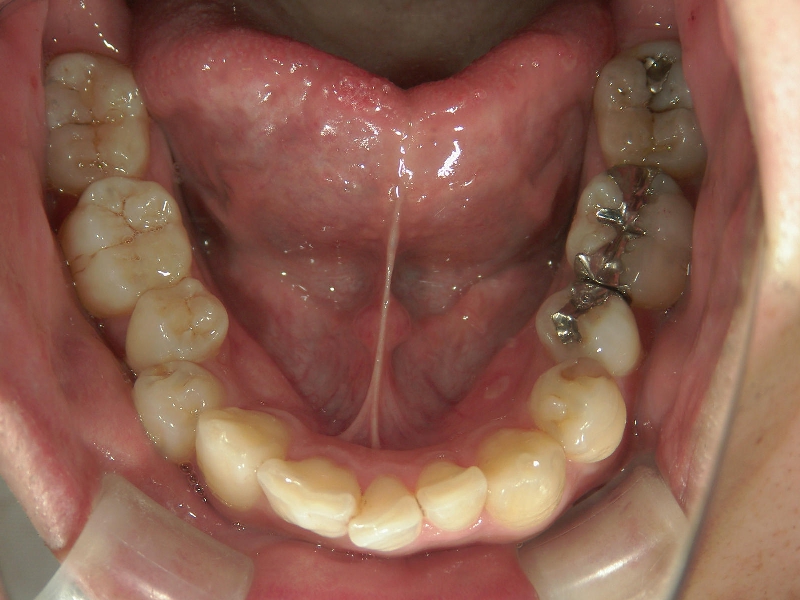

矯正_灰色.pngno.24_8228_治療前_下.jpg矯正_灰色.png